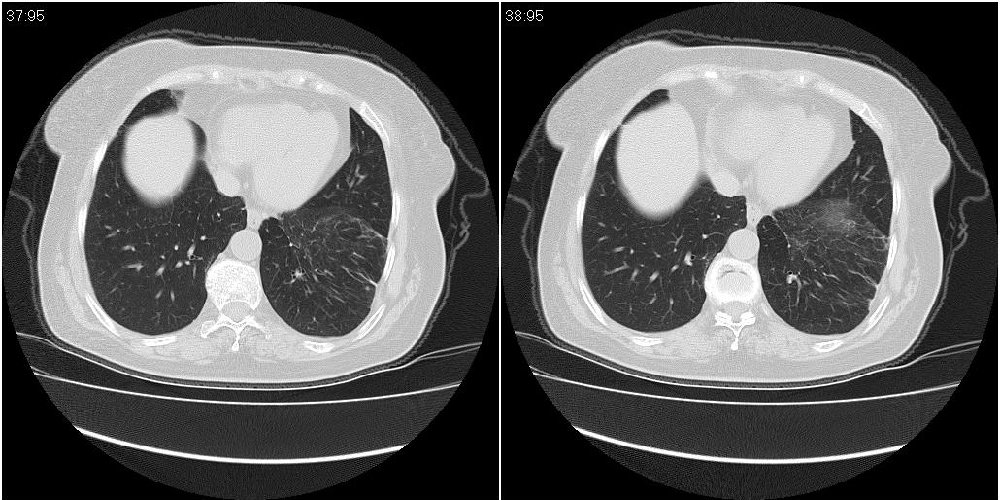

女性,72岁。去年9月份发现肺部病变,诊为肺结核并进行正规治疗至今,但复查后发现ct表现几乎没有变化。

双肺继发型tb并右中叶内膜tb,轻度支扩,左下胸膜肥厚粘连。

双肺继发性肺结核并右肺中叶节段性肺不张,左下胸膜肥厚粘连。

双肺继发性肺结核并右肺中叶节段性肺不张